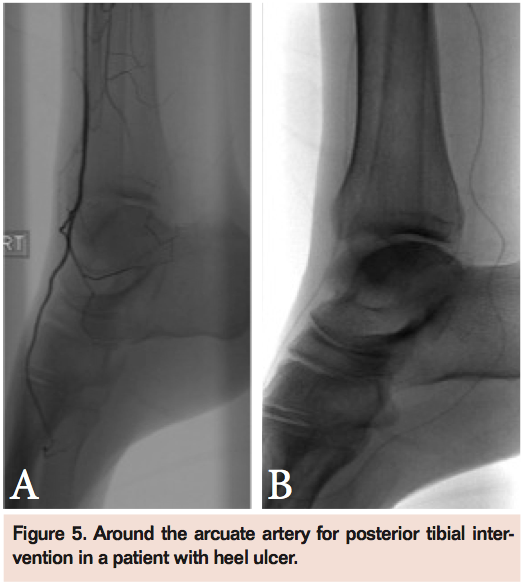

With currently available microcatheters and 0.014 systems, as well as improved imaging, the ability to intervene on tibial vessels is nearly limitless. Given the ability to treat this disease it would be wise to adhere to a few tips (Table 1). In tibial disease a luminal first strategy is preferred to subintimal techniques. Re-entry can often be much more difficult in the small distal tibial arteries. Realize that patience and selective imaging are more important in this vascular bed than more proximal occlusive disease. Initial proximal images may suggest long-segment occlusion. However distal catheter position may uncover treatable segments of disease (Figure 3). If the patient has severe multi-level peripheral arterial disease poor proximal flow can limit distal imaging. In this scenario we often traverse the proximal disease and uncover distal targets for surgical or endovascular revascularization (Figure 4). If we want to be aggressive at endovascular therapy then we have to consider less traditional approaches to reach target lesions (Figures 5 and 6). Pedal access can usually be achieved with a micropuncture set aiming for the contrast column on selected injections. This can then be upsized to facilitate retrograde crossing of occlusions.